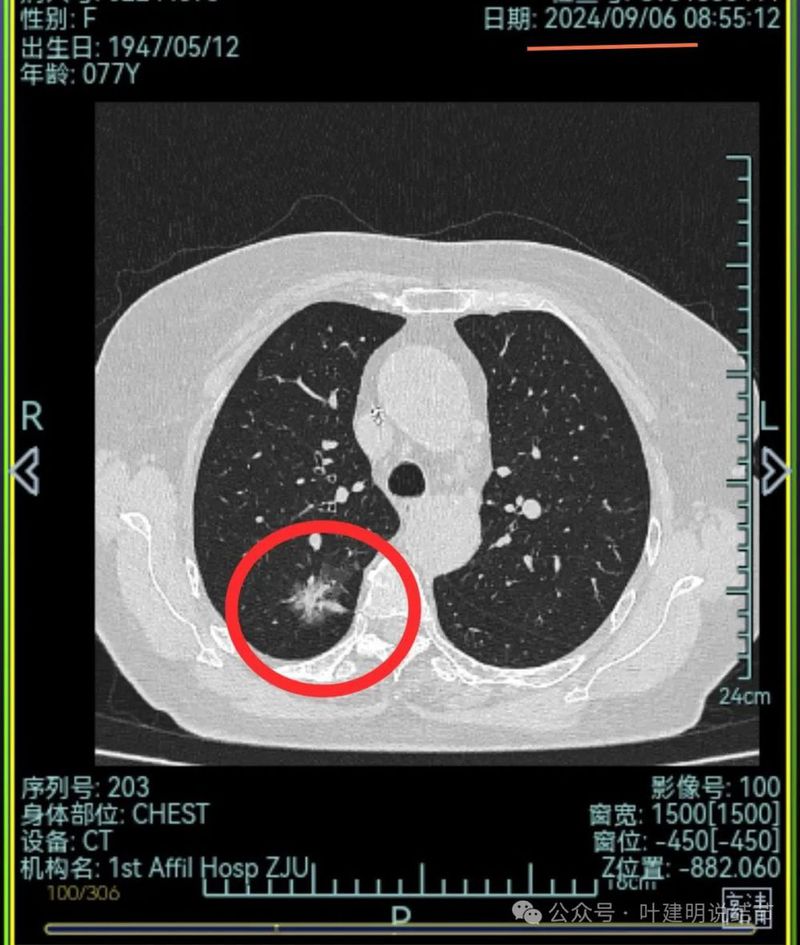

再来看2024年9月时的关键影像:

右上后段灶病灶不单没有好转,灶内密度是有增加进展的!

中叶处病灶不见了。

下叶背段伴血管征的病灶也不见了。

现在的影像考虑:

不单是右中叶以及右下叶的病灶吸收消失了,两肺其他病灶也基本上都不见了,唯独右上后段的病灶仍在而且有进展!再加上此灶原来单看也像恶性的,所以这位结友是感染与肿瘤并存,右上病灶基本上肯定是恶性的,而且是浸润性腺癌。

主病灶连续层面展示分析:

病灶出现,磨玻璃密度,轮廓与边界均清楚,灶内密度稍不均。

有明显血管进入,表面分叶,边缘不平,整体轮廓清。

边缘毛刺、表面不平、灶内偏实性成分、分叶明显,整体轮廓与瘤肺边界较为清楚。

灶内细支气管扩张、边缘毛刺较为锐利、有明显磨玻璃成分,磨玻璃成分的瘤肺边界清楚,病灶分叶明显。

灶内密度杂乱不均,内有小空泡征,表面不平。

灶内血管增粗穿行、磨玻璃成分明显,轮廓较清。

血管进入,磨玻璃成分,支气管扩张,边缘不平。

典型混合密度病灶,中间部分密度高偏实性,外围部分磨玻璃密度,两者之间交错存在,说明偏实性部分有侵袭性。磨玻璃成分与正常肺组织之间界限清楚,表面分叶,部分边缘毛刺,整体轮廓清。是非常符合恶性的影像表现。

灶内磨玻璃成分明显,并有异常增粗血管僵硬穿行于病灶内,支气管有扩张通气征,瘤肺边界清楚,实性成分明显。

影像再判断:

此灶连续层面上看已经是非常典型的恶性表现,再加上从发现到此次复查已经过去20个月,那是持续存在并有进展的。而同期发现的其他病灶都吸收消失了!由于仍有较多占比的磨玻璃成分,考虑仍是早期肺癌,转移的概率不大。如果我来决定,那是要考虑手术的,什么增强或PET-CT价值都不是很大,当然要查下也没什么坏处。

如果单单看2021年的,两肺多发混合磨玻璃密度阴影,那时候的影像比较难以判断红色支出一定是肺癌。但是经过随访,原来绿色的病毒性炎症的地方都吸收了,和红色这处没有好转。这一处是混合磨玻璃密度,表面不平,有毛刺征,有磨玻璃成分,病灶内部密度不均匀,是挺典型的浸润性腺癌的影像表现。位置靠背侧边缘比较近,能够单孔胸腔镜下楔形切除。我的想法还是尽早手术切除更为彻底。这种密度与形态大概率仍然是早期,一般不大容易会有转移,PET也没有说考虑有淋巴结或者远处转移。单孔局部楔形切掉效果肯定比消融或者立体定向放疗更加确切彻底。意见供参考!